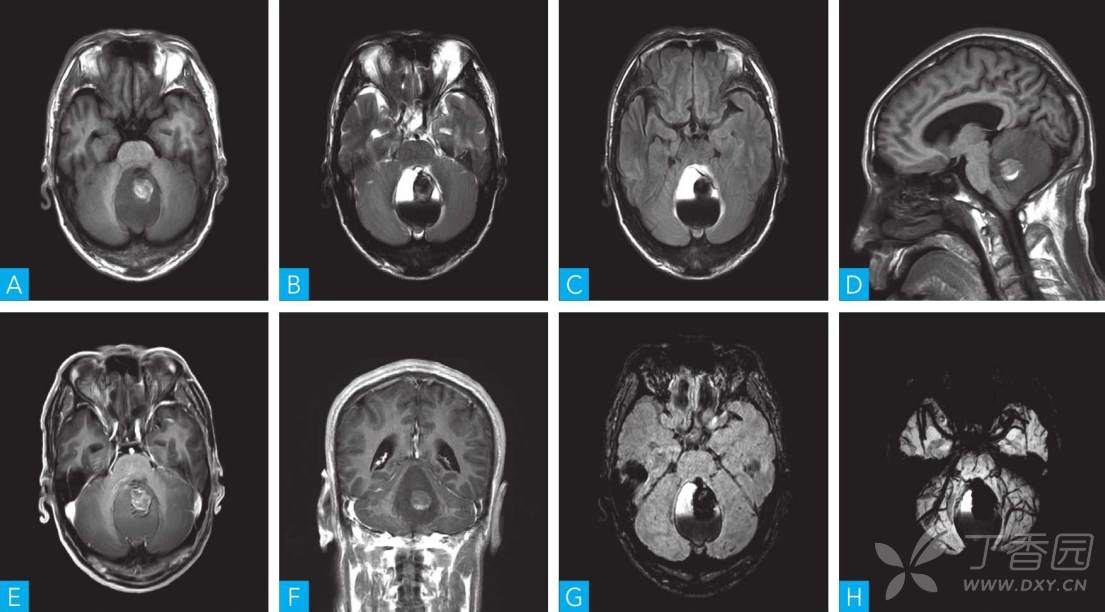

男性, 50岁。 间断头痛伴头晕6年余, 加重1周。 既往6年前无明显诱因头痛, 为阵发性枕部胀痛伴头晕, 经输液治疗症状好转, 后间断反复发作, 1周前症状加重伴走路不稳。 无视力模糊及视物旋转, 无幻嗅等。 既往史: 阑尾炎手术5年余, 高血压病史2年。

A.轴位T1WI; B.轴位T2WI; C.轴位T2-FLAIR; D.矢状位T1WI; E.轴位T1WI增强; F.冠状位T1WI增强; G, H. SWI